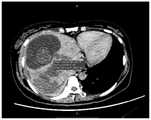

FIG. 3 is a CT image of the liver and surrounding tissue according to one embodiment of the present application;

The target puncture path is a tissue path through which a puncture needle passes when a target object (human or animal body) is punctured. The target puncture path may be stored in advance in a memory of the computer device, or may be acquired by a server or the like at the time of use. The target puncture path is an item in the surgical plan. The surgical plan may also include needle access points, target points, etc. The puncture path is different according to the difference of the needle inlet point and the target point. Referring to fig. 2, fig. 2 is a CT image of liver and surrounding area of a liver cancer patient after tumor embolization according to an embodiment. In the figure, from outside to inside, the following are in sequence: skin, subcutaneous tissue, liver capsule, normal liver, tumor caused by embolism and necrosis. Taking fig. 2 as an example, if an ablation operation needs to be performed on a patient, a puncture path is established, and the following tissues can be sequentially passed through: skin, subcutaneous tissue, muscle, fat, liver envelope, normal liver, ablation target.

Specifically, CT image data of the target object may be acquired, and in the CT image data, a CT value of the tissue passing through the target puncture path is extracted. Referring to fig. 7, fig. 7 is a CT image of a liver of a patient after embolization according to an embodiment. The CT device can automatically acquire data such as CT values corresponding to tissues passed by the puncture path in the image.